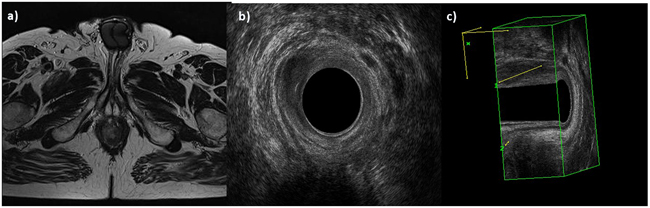

EAUS and MRI identified the involvement of anal verge in 28 (48.3%) patients, of anorectal junction in 17 (29.3%) patients, of internal sphincter in 54 (93.0%) patients (Figure 1) and of external sphincter in 47 (81.0%), with a correlation of 100%.

Figure 1: Man 42y, anal cancer. In a. TSE T2-W in axial plane, the lesion infiltrates internal and external sphincters, as showed also by 2 D b. and 3D c. EAUS.